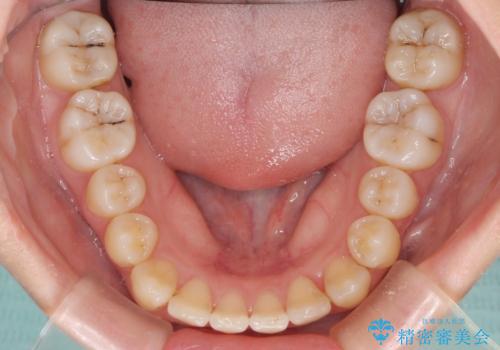

非常にしっかりとマウスピースを装着してくださいましたが、前歯の排列がなかなか仕上がらずに期間がかかってしまいました。